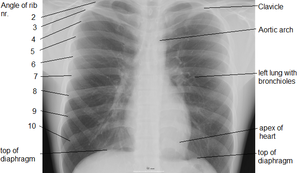

X-ray of chest, showing top of diaphragm.

وهو عضلة مخططة ( اي من النو ع الذي تستطيع ان تتحكم به اراديا ) لكنه يمكن ان يتحرك بدون ان تتحكم به اراديا ايضا . فممكن ان تتحكم بسرعة التنفس فتبعث الاوامر من منطقة الحركة في قشرة المخ ، وعندما تنام فان الاروامر تستمر من ال Medulla و Pons وهي مراكز التنفس في الدماغ . تلتصق عضلة الحجاب الحاجز بالسطح الداخلي من الاضلاع الستة السفلى ، والفقرات الاثنين او الثلاثة الصدرية العليا ، واسفل عظم الصدر الامامي Xyphoid Process و Lumbosacral Ligament . تصعد الياف العضلة إلى فوق ثم تلتحم مع بعضهما في رباط في الوسط The Central Tendonوتكون في الجهة اليمنى اعلى من الجهة اليسرى ( المكان الذي تغطي فيه الكبد ) ويكون هذا الاختلاف واضحا في اشعة الصدر . عندما يأخذ المرء نفسًا يتقلص الحجاب الحاجز ويتحرك إلى أسفل، وهذا يزيد مساحة الفراغ في الصدر. وفي الوقت ذاته، فإن العضلات المرتبطة بالأضلاع تجعل الأضلاع تتحرك نحو الخارج. وهذا من شأنه أن يوسع الصدر ويخلق مع حركة الحجاب الحاجز باتجاه الأسفل فراغًا بسيطًا في الصدر. ويجعل هذا الفراغ الهواء يدخل الرئتين عبر القصبة الهوائية، وهذا العمل ىُدعى التنفس أو الشهيق. وفي أثناء الزفير يخرج الهواء من الرئتين، عندما ينبسط الحجاب الحاجز وعضلات الأضلاع. وعندما يتنفس المرء بشكل طبيعي، يكون الزفير في حالة سلبية والعضلات دون عمل. وتحتوي الرئة المتوسعة على ألياف مرنة كانت قد تمددت أثناء التنفس. وهذا النسيج المرن يشبه في سلوكه الخيوط المطاطية المشدودة، ويجعل الرئة تتقلص كالبالون المنكمش. وهذا يطرد الهواء خارج الصدر، وتصغر الرئة حتى تصل إلى الحجم الذي بدأ فيه التنفس. ولاتفرغ الرئتان بشكل كامل أثناء الزفير لأن جدار الصدر يبقيها في حالة متمددة جزئيًا. ويكون الزفير نشطًا أثناء التنفس الشديد الذي يحدث أثناء التمارين الرياضية. وهناك مجموعة أخرى من عضلات الأضلاع تساعد في جعل الصدر أصغر، كما أن العضلات في جدار البطن تتقلص لتدفع بالأعضاء البطنية إلى أعلى أمام الحجاب الحاجز، وتساعد بذلك على إخراج الهواء من الرئتين.